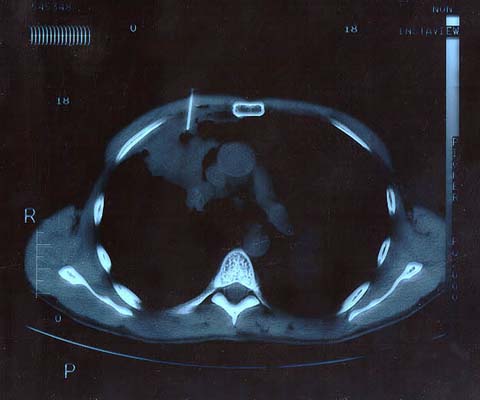

Scan 25th March 1999 No1